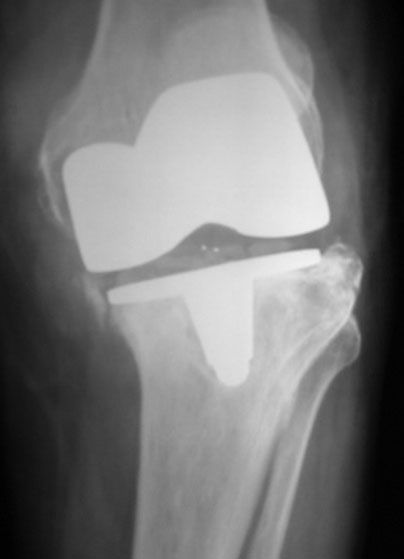

Failed TKR